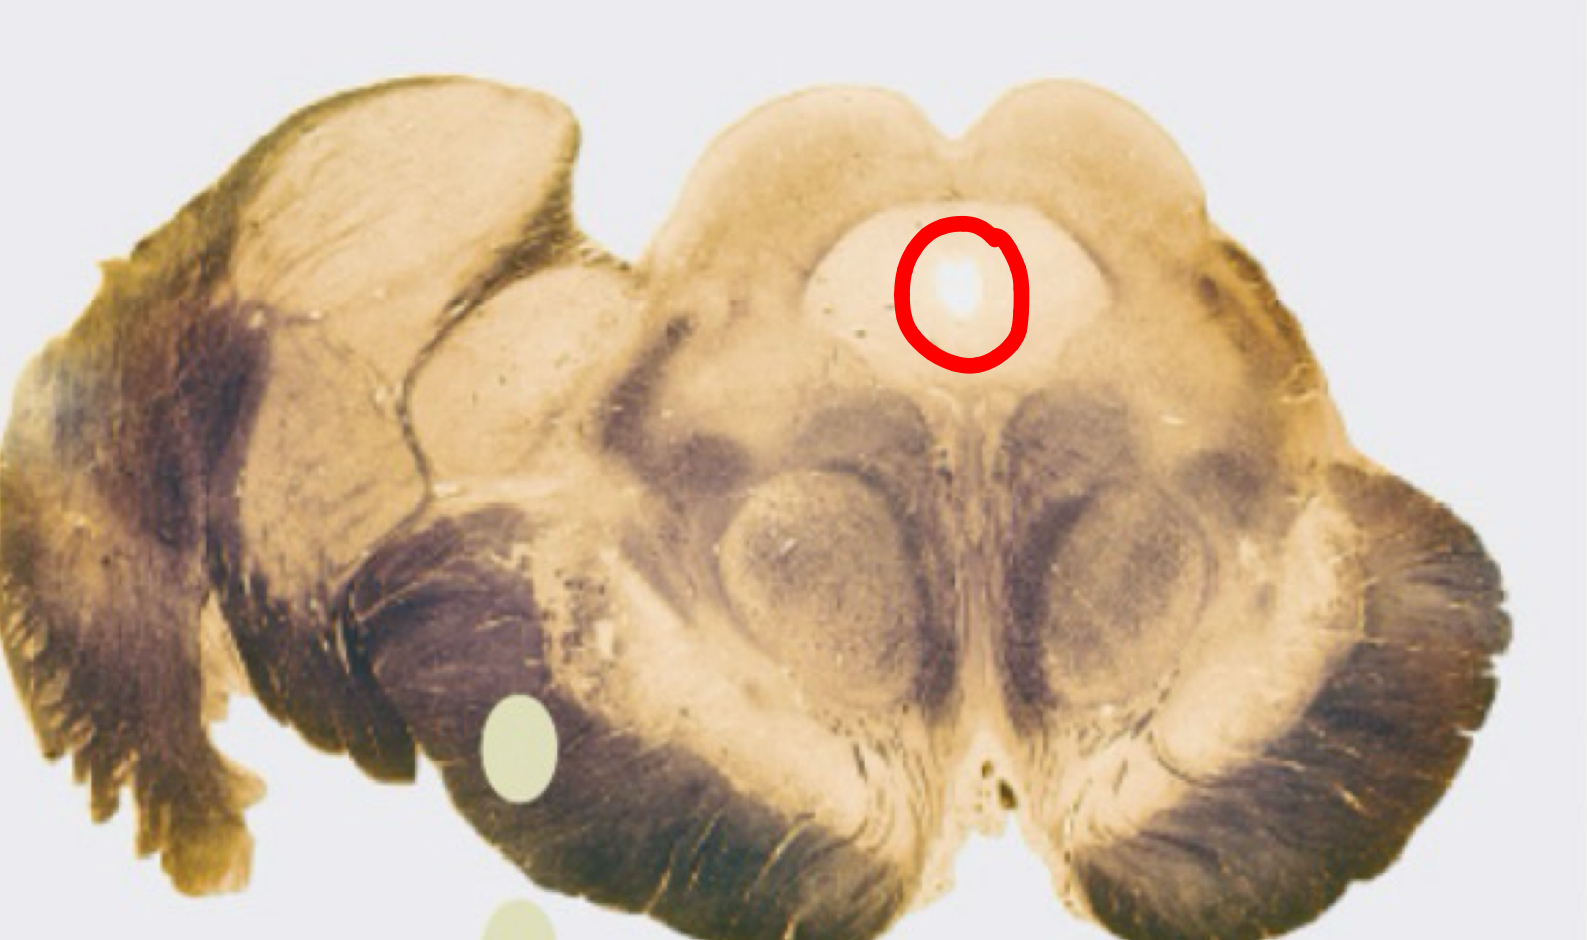

peri aqueductal grey rostral midbrain

red nucleus (mickey’s eyes hehe) rostral medulla

substantia nigra rostral midbrain

corticospinal + corticobulbar tracts rostral midbrain